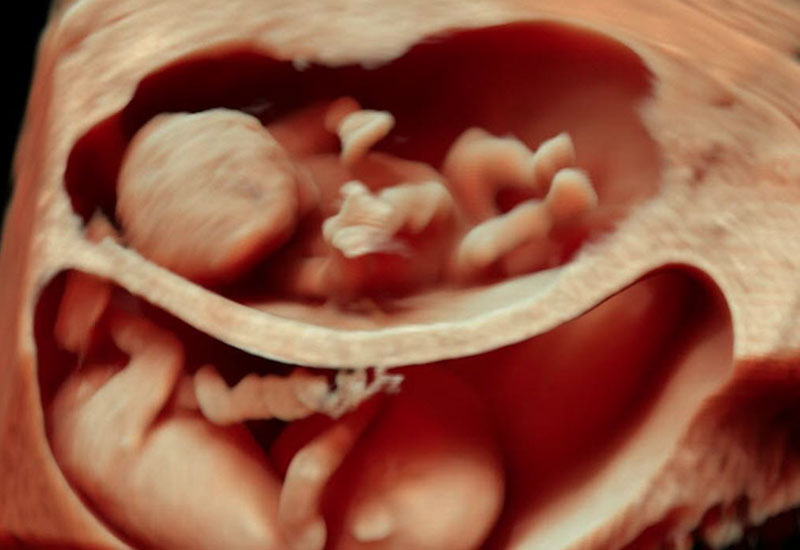

Twin-to-Twin Transfusion Syndrome (TTTS) Monitoring

In monochorionic twin pregnancies, TTTS is a serious condition caused by abnormal placental blood vessel connections. Regular surveillance allows early detection based on amniotic fluid imbalance, bladder visibility, and Doppler abnormalities, enabling timely referral for fetal therapy when needed.

Higher-Order Pregnancy Surveillance (Triplets & Above)

Higher-order pregnancies require even more intensive surveillance due to significant maternal and fetal risks. Dr. Ashwini Rathi provides individualized scanning schedules with advanced Doppler and growth monitoring tailored to each pregnancy.